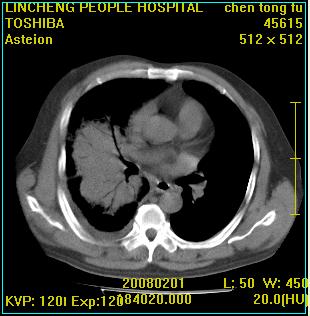

患者,男性,62岁。主因头晕,发热,咳嗽6天,高热达39度,esr19mm/h,wbc 3.9×10 9/l

实变区见空气支气管征,支气管通畅,考虑为大叶性肺炎,右侧少量胸水

1)考虑为:右肺感染性病变。建议:抗炎治疗复查。2)右侧少量胸腔积液。

实变区见空气支气管征,支气管通畅,考虑为大叶性肺炎,右侧少量胸水。